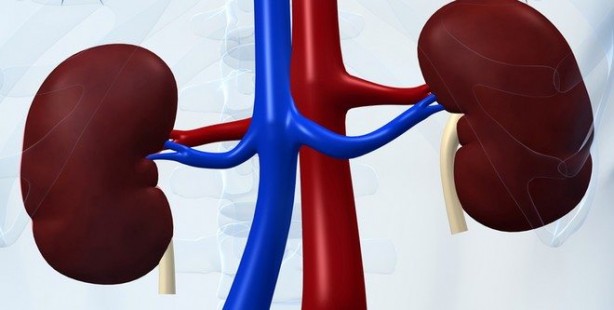

Böbrekleri koruyan 14 besin

Böbrek hastalıkları yaygın bir şekilde görülür. Sağlıklı beslenmeyle böbrekleri korumak mümkün. İşte böbreklere iyi gelen 14 besin.

Böbreklerin işleyişini kolaylaştırmak için sağlıklı beslenmek ve düzenli olarak su içmek çok önemlidir. Uzmanlar, gün boyunca en az 2,5 litre svı alınmasını önermektedir. Spor yapıyorsanız veya hava çok sıcaksa, miktarı biraz artırmak daha iyidir.